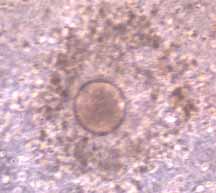

Mature Human

Egg

- large egg in comparison to surrounding

granulosa cells.